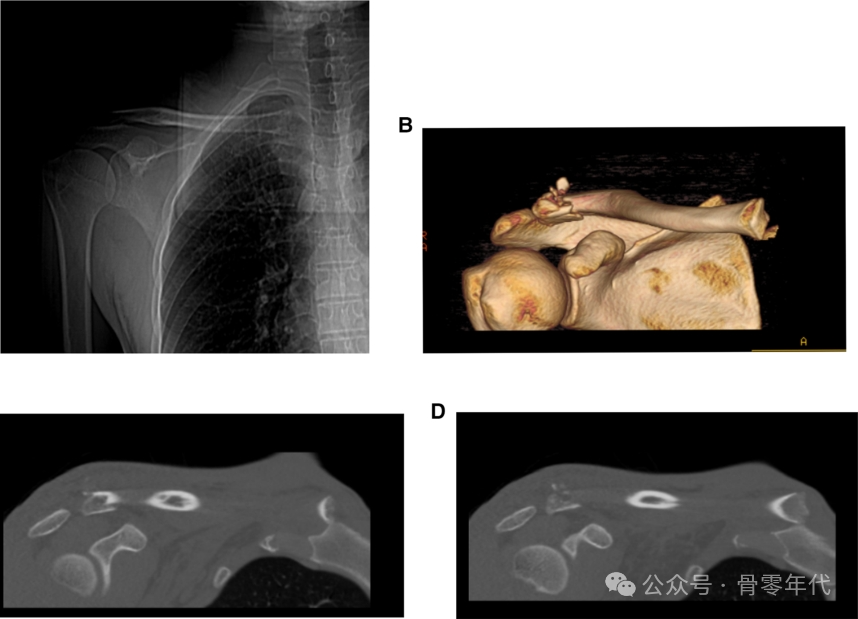

一名56岁的保安在从电动自行车上摔下,右肩疼痛来到医院就诊。在患者的标准X线片上,锁骨骨折的近端和远端均被分离。CT从不同角度显示锁骨骨折移位情况。术后骨折线、脱位均恢复。

1例锁骨远端骨折伴锁骨近端脱位患者的影像表现。钢板内固定治疗双极锁骨损伤1例。利用杠杆复位锁骨两端,然后分别放置新的胸锁钢板和肩锁钢板。术后对患者进行影像检查。X线和CT图像